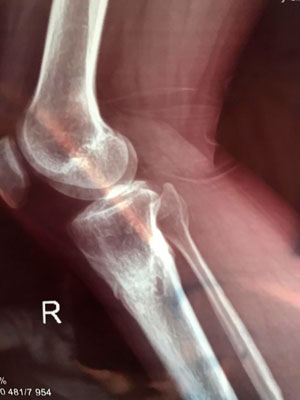

Исходник - 38 лет. Алматы.

Дата операции - 15.06.2019г.

на фиксации

Дата снятия аппаратов - 25.09.2019г.

Срок сращения - 100 дней.